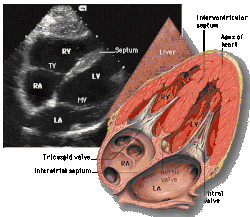

Subcostal four chamber

Each figure contains a TTE with a black background, and a corresponding colored illustration. Patrick J. Lynch and C. Carl Jaffe, Yale University, 2006.

Click on a figure to enlarge it and see some parts of the heart identified. RV, right ventricle; LV, left ventricle; RA, right atrium; LA, left atrium; TV, tricuspid valve; MV, mitral valve; AV, aortic valve; RVOT, right ventricular outflow tract; LVOT, left ventricular outflow tract